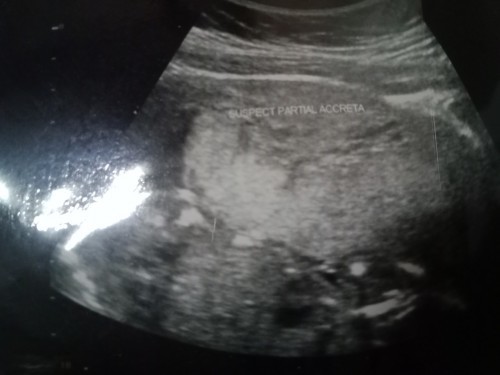

suspect partial Accreta แปลว่าอะไรค่ะ ในใบอัลตร้าซาวด์ แม่ๆคนไหนพอจะทราบมั้งค่ะ

สงสัยภาวะรกเกาะลึก(ไม่มาก)ค่ะ